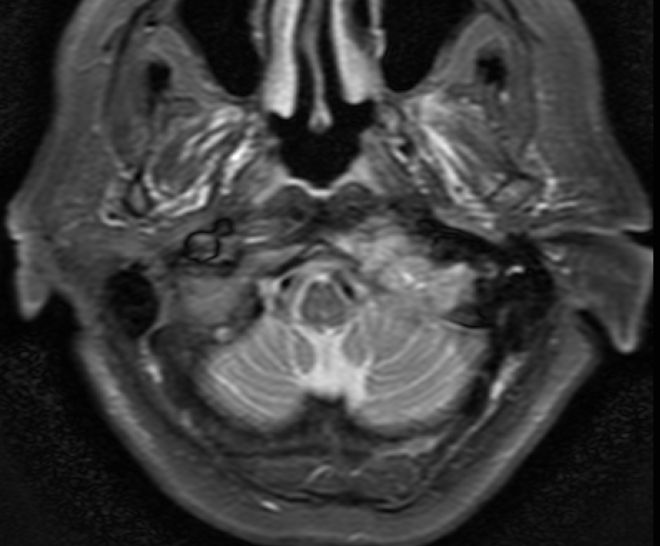

| MRT | Knochenmetastasen